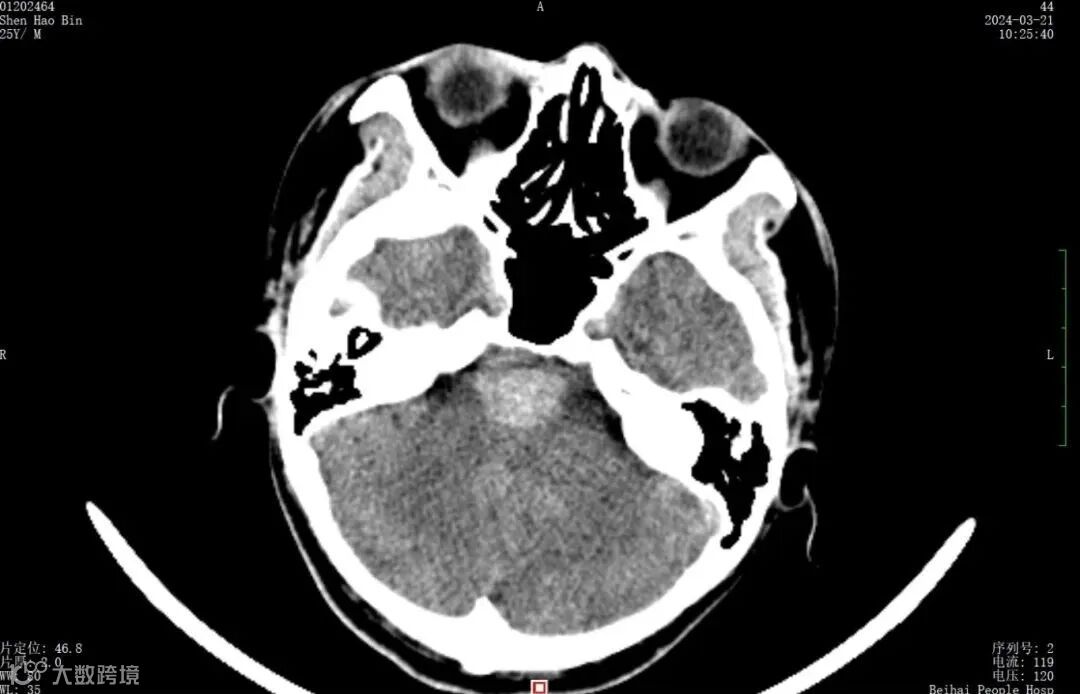

北海25岁男青年头痛5天,检查原来是脑出血